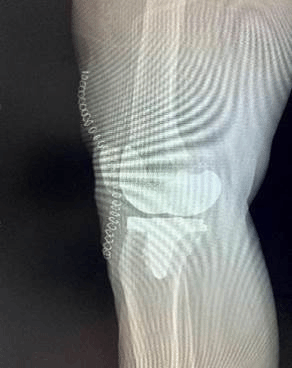

术后:

(图六)术后患者X光影相